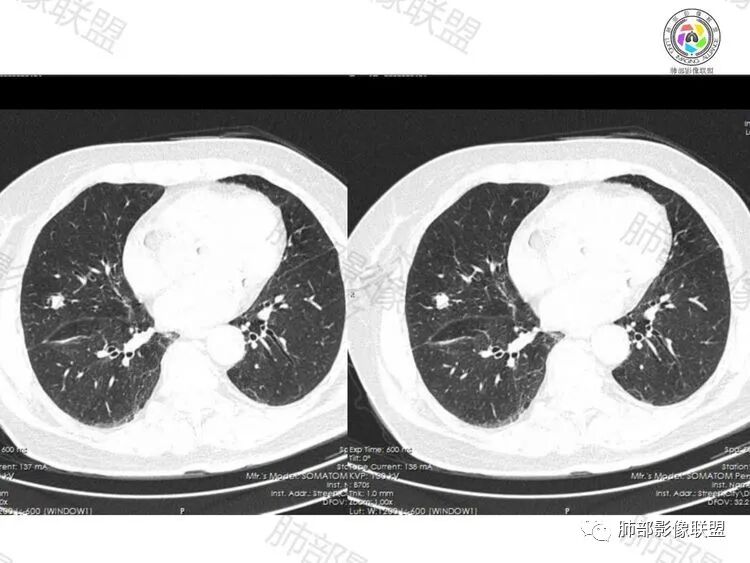

1.腺癌:有时可见边缘清楚GGO晕。收缩力常较明显已出现胸膜凹陷,常见深分叶及粗短毛刺,有时可见空泡征。当腺癌表现为实性成分多时,脐凹征及异常血供多可提示诊断。低分化腺癌全实性成分,有时收缩力不明显。出现淋巴管炎及胸膜、叶间裂多发结节时,常高度提示腺癌可能。

2.结核:当结核灶纤维成分增多,可表现为明显的收缩力。结核灶常密度不均,易出现干酪性坏死及钙化,当出现长索条、钙化灶、周围卫星灶多可提示诊断,当出现空洞时,其内壁多光滑。

3.隐球:此例有多结节融合感,有“蘑菇兄弟”,隐球需要考虑,但隐球多无明显收缩力,周围有晕,毛刺细软,支气管多不受累及,多分布在外围及胸膜下,可以提示诊断。

4.慢性非特异性炎症:慢性非特异性炎多为肺部炎症、吸收、机化、最后纤维化发展而来,因初发炎症多表现为片状或大片状,故其吸收、修复后多表现为条状或长索条状影,当表现为结节时,其毛刺粗长,初发炎症坏死越多,其最后表现为慢性非特异性炎其实性成分越多,其内部多为纤维成分,故其强化多为渐进性强化。本例病理为慢性炎症。

综上,此例考虑为炎性,腺癌不能完全除外。当实性结节不能排除新生物且抗炎治疗无效时,应积极获得病理学依据。

本例穿刺病理结果提示慢性炎,小编认为还需年度随访更为稳妥些。